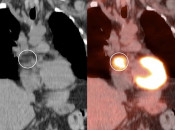

LHIAS is focal fatty infiltration of the inter-atrial septum of the heart.  It behaves as hypermetabolic brown fat, and is often intensely FDG-avid, appearing mass-like on the PET images.

Diagnosis of this hypermetabolic PET finding is confirmed by the presence of only fat on the co-registered CT images.